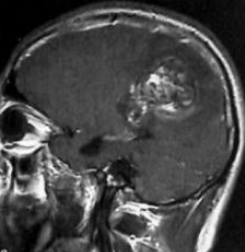

像麦凯恩所患的胶质瘤类型为原发性胶质母细胞瘤,属于WHOⅣ级,是恶性程度较高的胶质瘤。胶质母细胞瘤生长速度快、病程短,70%~80%患者病程在3~6个月,病程超过1年者仅10%。胶质母细胞瘤患者经肿瘤肉眼全切放疗、化疗等综合治疗后,2年生存率为10%,有不到5%的患者可长期生存。

夺走多位名人生命的病魔胶质瘤,有方法治愈吗?胶质瘤是较常见的颅内肿瘤,胶质瘤在临床上分为4级,并不是每一级别都难以治疗。其中I、II级偏良性,预后好,及时治疗,很大机会能够治愈。但III、IV级就比较危险,由于已经到晚期,治疗难度很大,而且手术后需要辅助放疗和化疗,即便如此,只要切除率未达到全切,肿瘤复发率仍然较高,患者生存期也较短。所以对于胶质瘤患者来说,及早发现,及早治疗,在一二级时,是有很大机会治愈的。

目前对于胶质瘤的治疗,优选治疗便是手术,以较大范围顺利切除肿瘤为手术基本原则。手术可以减轻肿瘤负荷、缓解颅高压等症状、明确组织学类型、为放化疗提供坚实基础。但是由于胶质瘤所处的位置-人体较重要的大脑。大脑是人体较复杂的器官,各种神经组织、器官、血管密布,手术时既要确定切除率,又要确定不损伤其他重要神经组织,所以手术难度是大的。